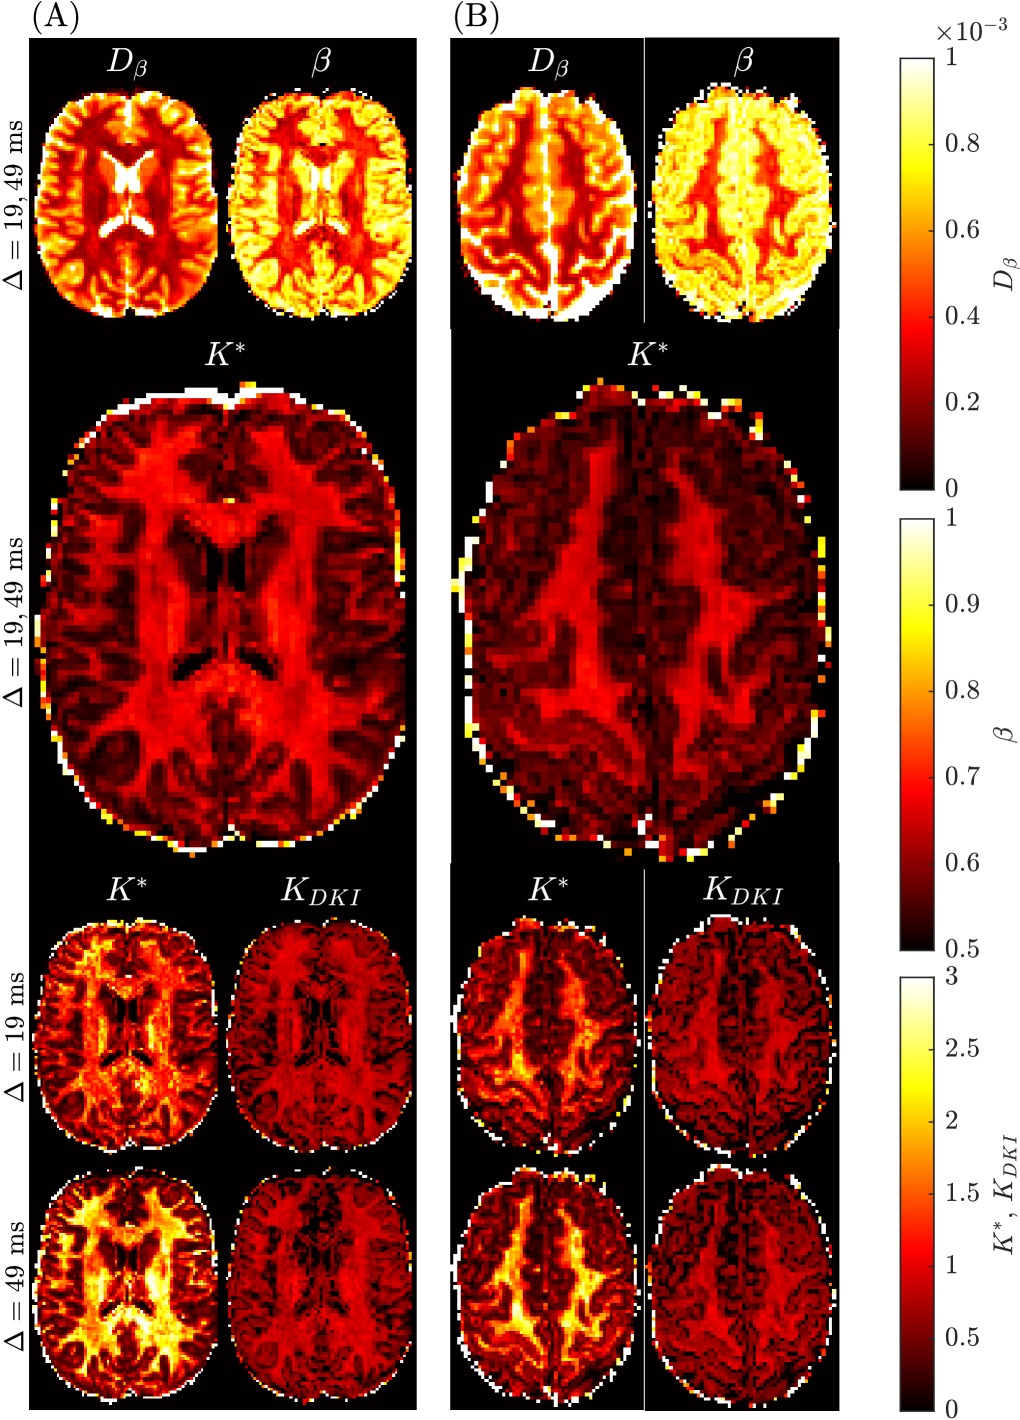

2.4 Benchmark mean kurtosis in the brain

The benchmark mean kurtosis estimation in the brain is established using the entire b-value range with all diffusion encoding directions available in the Connectome 1.0 DW-MRI data. For two subjects in different slices, Figure 6 provides the spatially resolved maps of mean kurtosis computed using the sub-diffusion method (i.e., Ksuperscript𝐾K^{*}italic_K start_POSTSUPERSCRIPT ∗ end_POSTSUPERSCRIPT) with one or two diffusion times, and using the standard method (i.e., KDKIsubscript𝐾𝐷𝐾𝐼K_{DKI}italic_K start_POSTSUBSCRIPT italic_D italic_K italic_I end_POSTSUBSCRIPT) considering the two distinct diffusion times. First, we notice a degradation in the KDKIsubscript𝐾𝐷𝐾𝐼K_{DKI}italic_K start_POSTSUBSCRIPT italic_D italic_K italic_I end_POSTSUBSCRIPT image with an increase in diffusion time. Second, the use of a single diffusion time with the sub-diffusion model leads to Ksuperscript𝐾K^{*}italic_K start_POSTSUPERSCRIPT ∗ end_POSTSUPERSCRIPT values which are larger than either the KDKIsubscript𝐾𝐷𝐾𝐼K_{DKI}italic_K start_POSTSUBSCRIPT italic_D italic_K italic_I end_POSTSUBSCRIPT values or Ksuperscript𝐾K^{*}italic_K start_POSTSUPERSCRIPT ∗ end_POSTSUPERSCRIPT values generated using two diffusion times. Third, the quality of the mean kurtosis map appears to visually be best when two diffusion times are used to estimate Ksuperscript𝐾K^{*}italic_K start_POSTSUPERSCRIPT ∗ end_POSTSUPERSCRIPT. Superior grey-white matter tissue contrast (TC) was found for the Ksuperscript𝐾K^{*}italic_K start_POSTSUPERSCRIPT ∗ end_POSTSUPERSCRIPT map (TC=1.73𝑇𝐶1.73TC=1.73italic_T italic_C = 1.73), compared to the KDKIsubscript𝐾𝐷𝐾𝐼K_{DKI}italic_K start_POSTSUBSCRIPT italic_D italic_K italic_I end_POSTSUBSCRIPT maps (TC=0.80𝑇𝐶0.80TC=0.80italic_T italic_C = 0.80 for the Δ=19 msΔ19 ms\Delta=19\text{ ms}roman_Δ = 19 ms dataset and TC=1.01𝑇𝐶1.01TC=1.01italic_T italic_C = 1.01 for the Δ=49 msΔ49 ms\Delta=49\text{ ms}roman_Δ = 49 ms dataset).

In Figure 7, an error map (measured by root- mean-square-error, RMSE) from Subject 5 slice 74 was presented for fitting the sub-diffusion model to the DW-MRI data with two diffusion times. Sample parameter fittings in both b-space (3) and q-space (4) were provided for four representative white and grey matter voxels.

Refer to caption

Figure 6: Spatially resolved maps of mean kurtosis shown for two example slices and two different subjects, Subject 3 rescan slice 71 (Panel A) and Subject 5 slice 74 (Panel B) from the Connectome 1.0 DW-MRI data. Individual maps were generated using the sub-diffusion model framework (Ksuperscript𝐾K^{*}italic_K start_POSTSUPERSCRIPT ∗ end_POSTSUPERSCRIPT), as well as using the traditional approach (KDKIsubscript𝐾𝐷𝐾𝐼K_{DKI}italic_K start_POSTSUBSCRIPT italic_D italic_K italic_I end_POSTSUBSCRIPT). The diffusion times, ΔΔ\Deltaroman_Δ, used to generate each plot are provided for each case. We consider the mean kurtosis maps using two diffusion times (Δ=19, 49msΔ1949ms\Delta=19,\leavevmode\nobreak\ 49$\mathrm{m}\mathrm{s}$roman_Δ = 19 , 49 roman_ms) as the benchmarks.

Quantitative findings for kurtosis are provided in Table 2. The analysis was performed for sub-cortical grey matter (scGM), cortical grey mater (cGM) and white matter (WM) brain regions. For specifics we refer the reader to the appropriate methods section. The table entries highlight the differences in mean kurtosis when computed using the two different approaches. The trend for the traditional single diffusion time approach is that an increase in ΔΔ\Deltaroman_Δ results in a slight decrease in the mean KDKIsubscript𝐾𝐷𝐾𝐼K_{DKI}italic_K start_POSTSUBSCRIPT italic_D italic_K italic_I end_POSTSUBSCRIPT, and an increase in the coefficient of variation (CV) for any region. For example, the mean KDKIsubscript𝐾𝐷𝐾𝐼K_{DKI}italic_K start_POSTSUBSCRIPT italic_D italic_K italic_I end_POSTSUBSCRIPT in the thalamus reduces from 0.650.650.650.65 to 0.580.580.580.58, while the CV increases from 30%percent3030\%30 % to 39%percent3939\%39 %. As much as 30%percent3030\%30 % increase in CV is common for scGM and cGM regions, and around 10%percent1010\%10 % for WM regions. The CV based on the Ksuperscript𝐾K^{*}italic_K start_POSTSUPERSCRIPT ∗ end_POSTSUPERSCRIPT value for each region is less than the CV for KDKIsubscript𝐾𝐷𝐾𝐼K_{DKI}italic_K start_POSTSUBSCRIPT italic_D italic_K italic_I end_POSTSUBSCRIPT with either Δ=19 msΔ19 ms\Delta=19\text{ ms}roman_Δ = 19 ms or Δ=49 msΔ49 ms\Delta=49\text{ ms}roman_Δ = 49 ms.

Figure 8 presents the distributions of the fitted parameters (D𝐷Ditalic_D and K𝐾Kitalic_K) in specific brain regions, based on the sub-diffusion model (panel A) and the standard DKI model with Δ=19 msΔ19 ms\Delta=19\text{ ms}roman_Δ = 19 ms (panel B). The distributions are colored by the probability density. Yellow indicates high probability density, light blue indicates low probability density. In each subplot, the diffusivity is plotted along the abscissa axis and the kurtosis is along the ordinate axis. Results for the standard DKI model with Δ=49 msΔ49 ms\Delta=49\text{ ms}roman_Δ = 49 ms are qualitatively similar, so are not shown here. From panel (B), we see an unknown nonlinear relationship between the DKI pair, DDKIsubscript𝐷𝐷𝐾𝐼D_{DKI}italic_D start_POSTSUBSCRIPT italic_D italic_K italic_I end_POSTSUBSCRIPT and KDKIsubscript𝐾𝐷𝐾𝐼K_{DKI}italic_K start_POSTSUBSCRIPT italic_D italic_K italic_I end_POSTSUBSCRIPT, in all regions considered. By comparison, the sub-diffusion based Ksuperscript𝐾K^{*}italic_K start_POSTSUPERSCRIPT ∗ end_POSTSUPERSCRIPT and Dsuperscript𝐷D^{*}italic_D start_POSTSUPERSCRIPT ∗ end_POSTSUPERSCRIPT (panel A) are less correlated with each other, indicating Dsuperscript𝐷D^{*}italic_D start_POSTSUPERSCRIPT ∗ end_POSTSUPERSCRIPT and Ksuperscript𝐾K^{*}italic_K start_POSTSUPERSCRIPT ∗ end_POSTSUPERSCRIPT carry distinct information, which will be very valuable for characterising tissue microstructure. Tables 3 and 4 present the Dβsubscript𝐷𝛽D_{\beta}italic_D start_POSTSUBSCRIPT italic_β end_POSTSUBSCRIPT and β𝛽\betaitalic_β values used to compute Dsuperscript𝐷D^{*}italic_D start_POSTSUPERSCRIPT ∗ end_POSTSUPERSCRIPT and Ksuperscript𝐾K^{*}italic_K start_POSTSUPERSCRIPT ∗ end_POSTSUPERSCRIPT in Table 2 and Figure 8 .